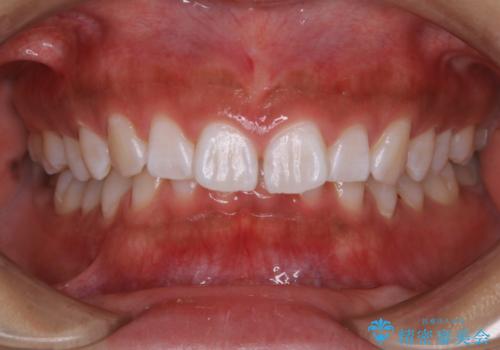

この患者様は、歯科矯正に1、2年かかり矯正中はホワイトニングをすることが出来ないため、歯を白くしてから矯正治療にすすみたいとのことでオフィスホワイトニングを行いました。1回の施術で2.3トーン白くなり、とても白くなりました。ホワイトニングは何度も重ねて白くしていくのですが、1度で満足のいく色見になったため一旦様子を見ることにしました。

1ヶ月後来院して頂きチェックしたところ、やはり後戻りがあったため、再度オフィスホワイトニングを行うことになりました。

1回のオフィスホワイトニングですとこのくらいの後戻りがあるため、ホワイトニングを考えている方は是非参考にしてください。